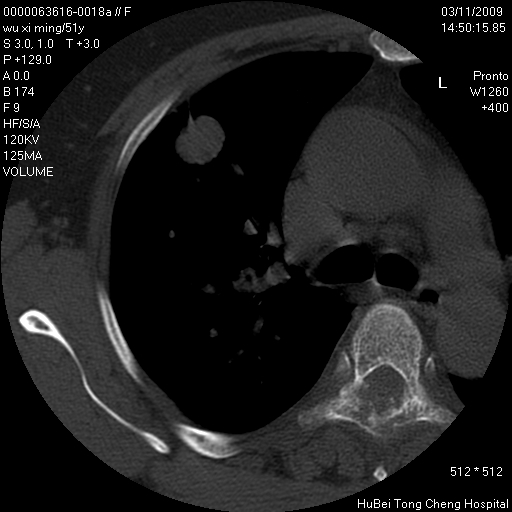

患者 女,51岁。因“胆囊炎,胆囊结石”,行常规术前胸部x线检查发现:右上肺结节病灶,建议行进一步检查。患者无咳嗽、咳痰及咯血等呼吸道症状,近期出现背部疼痛不适。

胸部ct轴位平扫(层厚10mm,螺距1.5,重建间隔10mm;部分层面:层厚3mm,螺距1.0,重建间隔3mm),图像如下:

1、周围型肺癌。(毛刺正、血管束集征,分叶。)

集束征,胸膜牽拉征,毛刺,淺分葉高度提示ca.

右肺周围型肺癌伴肺内转移及胸椎转移。已无手术机会。